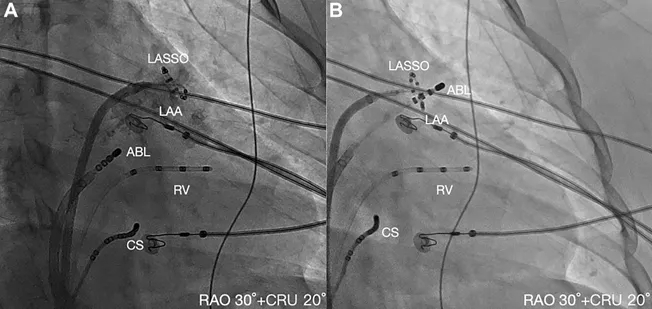

随后进行了心脏电生理检查与导管消融术。首先经房间隔穿刺后,将环状标测导管和压力感应消融导管送入左心房;在左心耳内用Lasso导管进行AT的激动标测,结果显示P波前存在近场电位,证实为左心耳局灶性起源,最早激动区域位于左心耳顶部(图2A和2B)。

图3透视下每根导管的具体位置

注:(A)左心耳造影以确认环状标测导管在左心耳内的准确定位。(B)将压力感知消融导管置于左心耳尖部进行消融